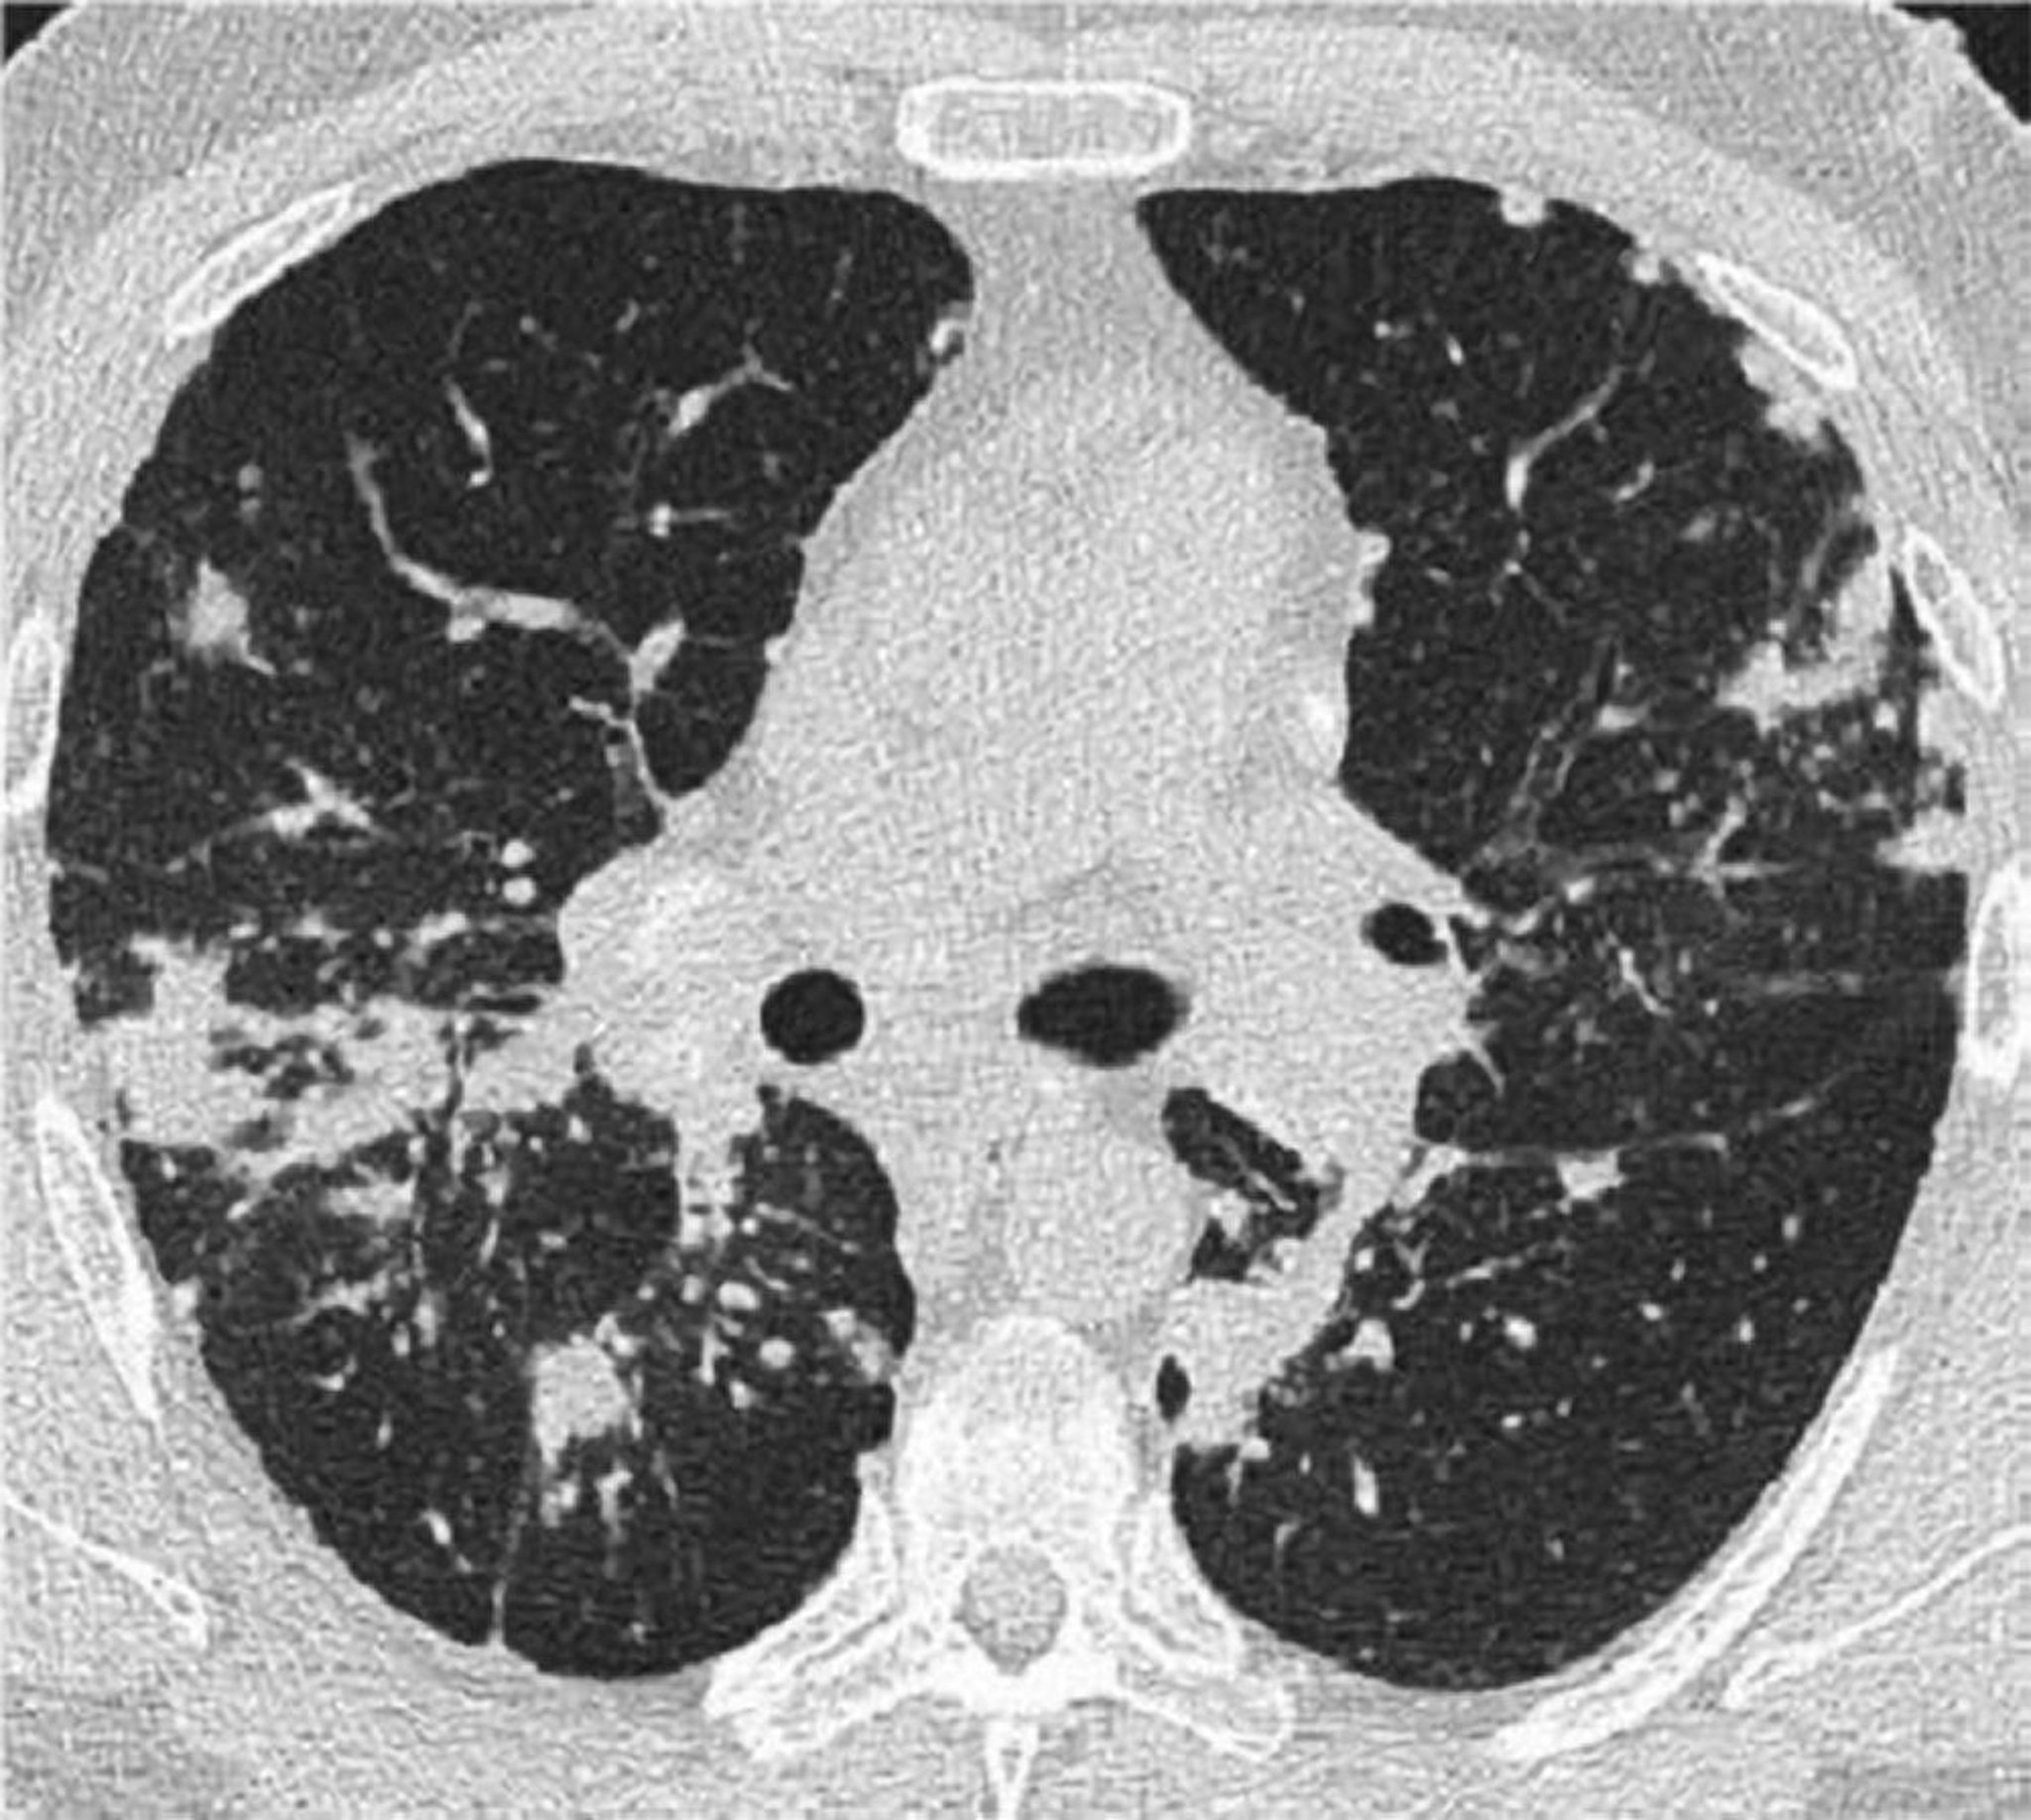

TC de tórax na sarcoidose pulmonar

Essa TC de alta resolução do tórax de um paciente com sarcoidose pulmonar mostra espessamento dos feixes broncovasculares e perolização dos septos interlobulares.

Imagem cedida por cortesia de Birendra P. Sah, MD, FCCP.